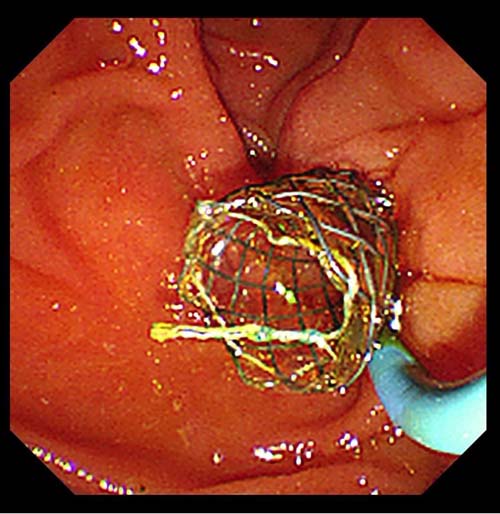

第一次ERCP胆道镜直视下

胆囊内可见多发褐色结石

我院消化内科在许洪伟主任带领下,各个亚专业蓬勃发展,胆胰内镜诊疗技术不断进步、提升。5月26日,消化内科中心院区胆胰疾病亚专科团队率先在省内开展了内镜下经纯自然腔道保胆取石术。该治疗技术是在ERCP基础上将胆道镜经十二指肠乳头开口逆行插入胆总管、胆囊管,并继续进入胆囊内进行探查、冲洗后留置导丝于胆囊内,沿导丝将可回收全覆膜金属支架置入于胆囊-胆囊管-胆总管-十二指肠乳头外,待支架完全扩张后再行胆道镜直视下胆囊取石,较大的结石先进行胆道镜直视下激光碎石再进行取石,较小的胆囊结石可通过支架自行排出或者通过胆道镜专用网篮取出,确定胆囊无结石后再将胆囊管支架取出即可。该技术无需腹壁开刀、打孔,体表无任何创口和疤痕,亦不对胃壁进行切开造成损伤,对于有保留胆囊需求的患者将是一个新的治疗选择。